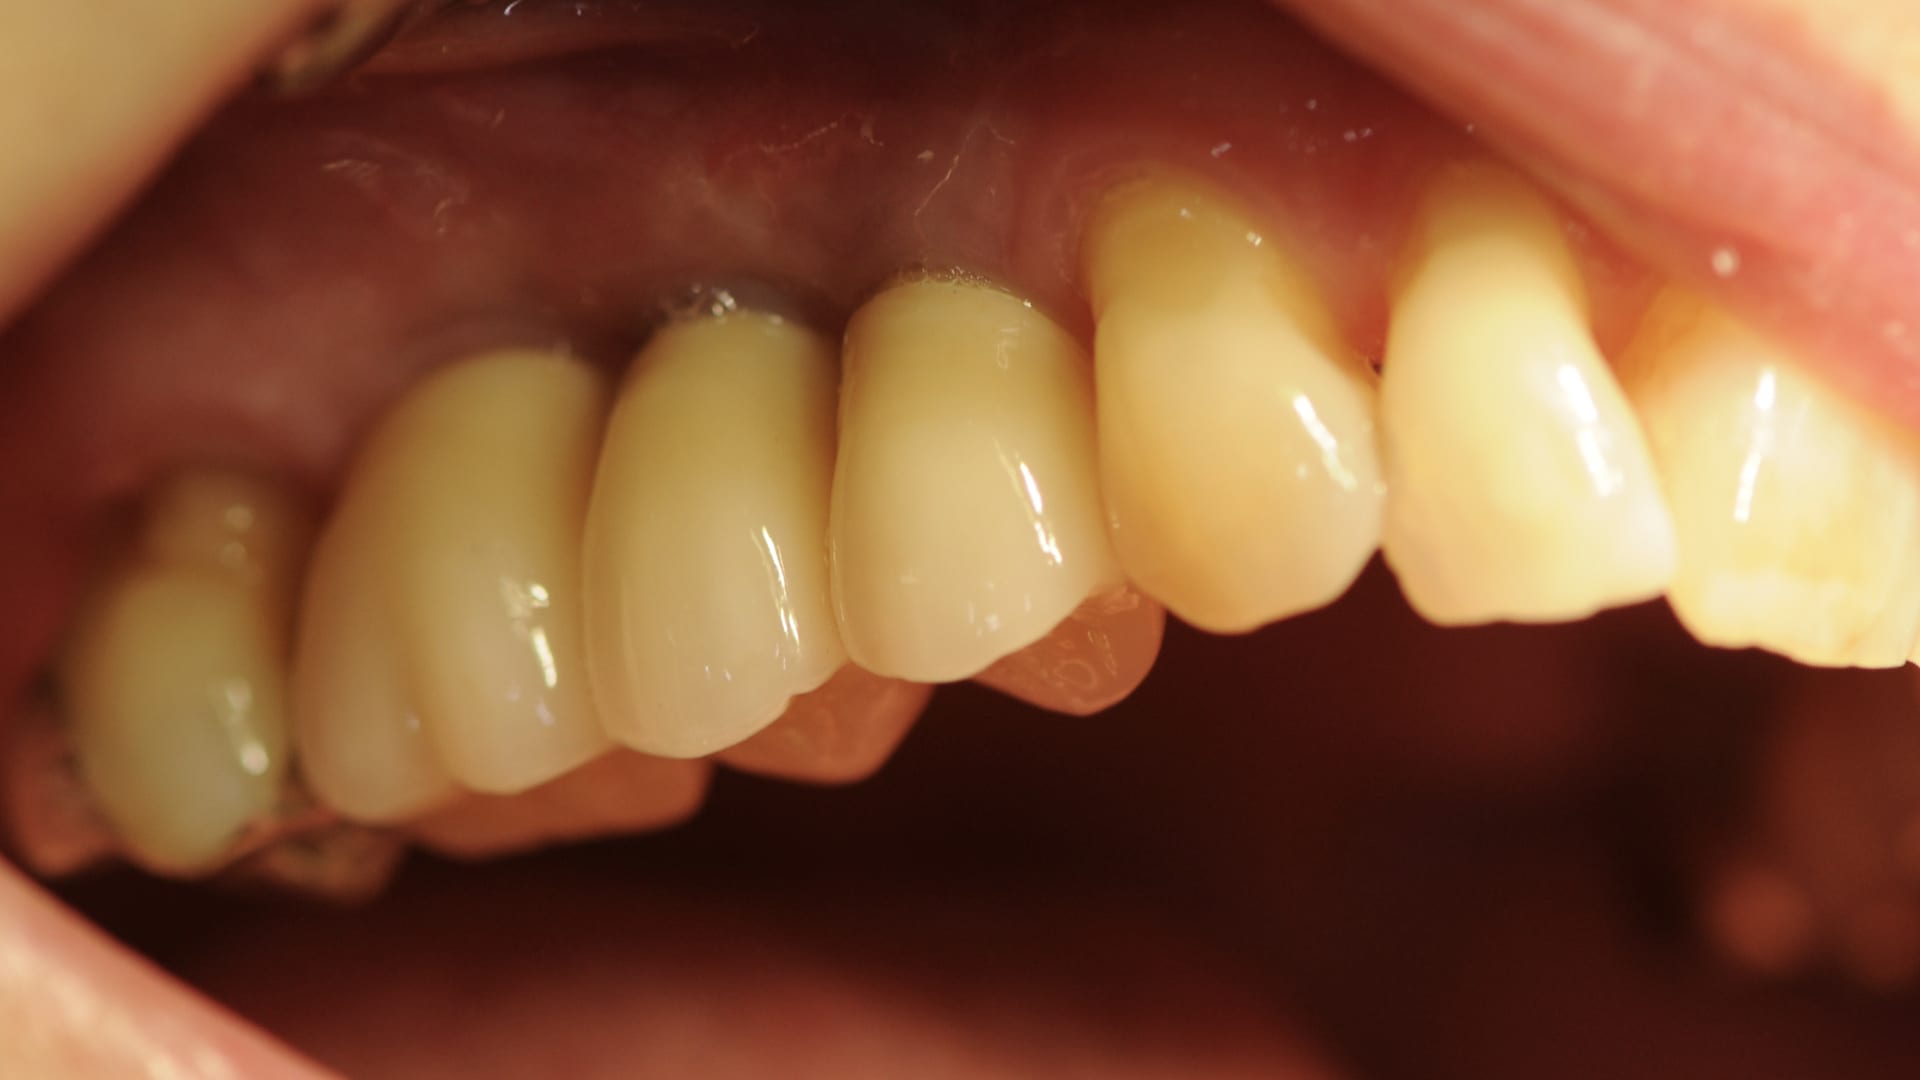

Abb. 19: Abschlussbild

Die erstellten digitalen STL-Daten der Modelle wurden in der CAM-Software des 3D-Druckers positioniert und zum Drucker gesendet. In der CAM-Software der Fräsmaschine erfolgte das Nesting der designten Abutments und Verblendkappen in einem Zirkonoxid-Block (Abb. 10 bis 12). Hier endete die digitale Prozesskette im vorliegenden Fall. Die gedruckten Modelle artikulierte das Dentallabor ein. Ebenso wurden die digitalen Laboranloge im Modell mit Pattern Resin fixiert. Die Aufbereitung der Abutments und die damit verbundene Güte der Oberfläche erfolgte nach dem von Rinke et al. erarbeiteten Protokoll. Zur Verbindung von Variobase und Zirkonoxid kam ein Multilink Hybrid-Abutmen zum Einsatz. Im Anschluss erfolgte die keramische Verblendung der anatomisch reduzierten Zirkonoxid-Kappen nach den Vorgaben des intraoralen Scans (Abb. 13) und der Versand in die Praxis (Abb. 14 und 15). Nach dem Einbringen der Abutments auf Klebebasis mit 35 Ncm (Abb. 16 bis 18) wurden die Schraubenkanäle mit Komposit verschlossen. Die definitiven Kronen wurden nach der Ästhetik-, Funktions- und Okklusionsprüfung mit implantlink semi Forte von Detax eingesetzt (Abb. 19 und 20).